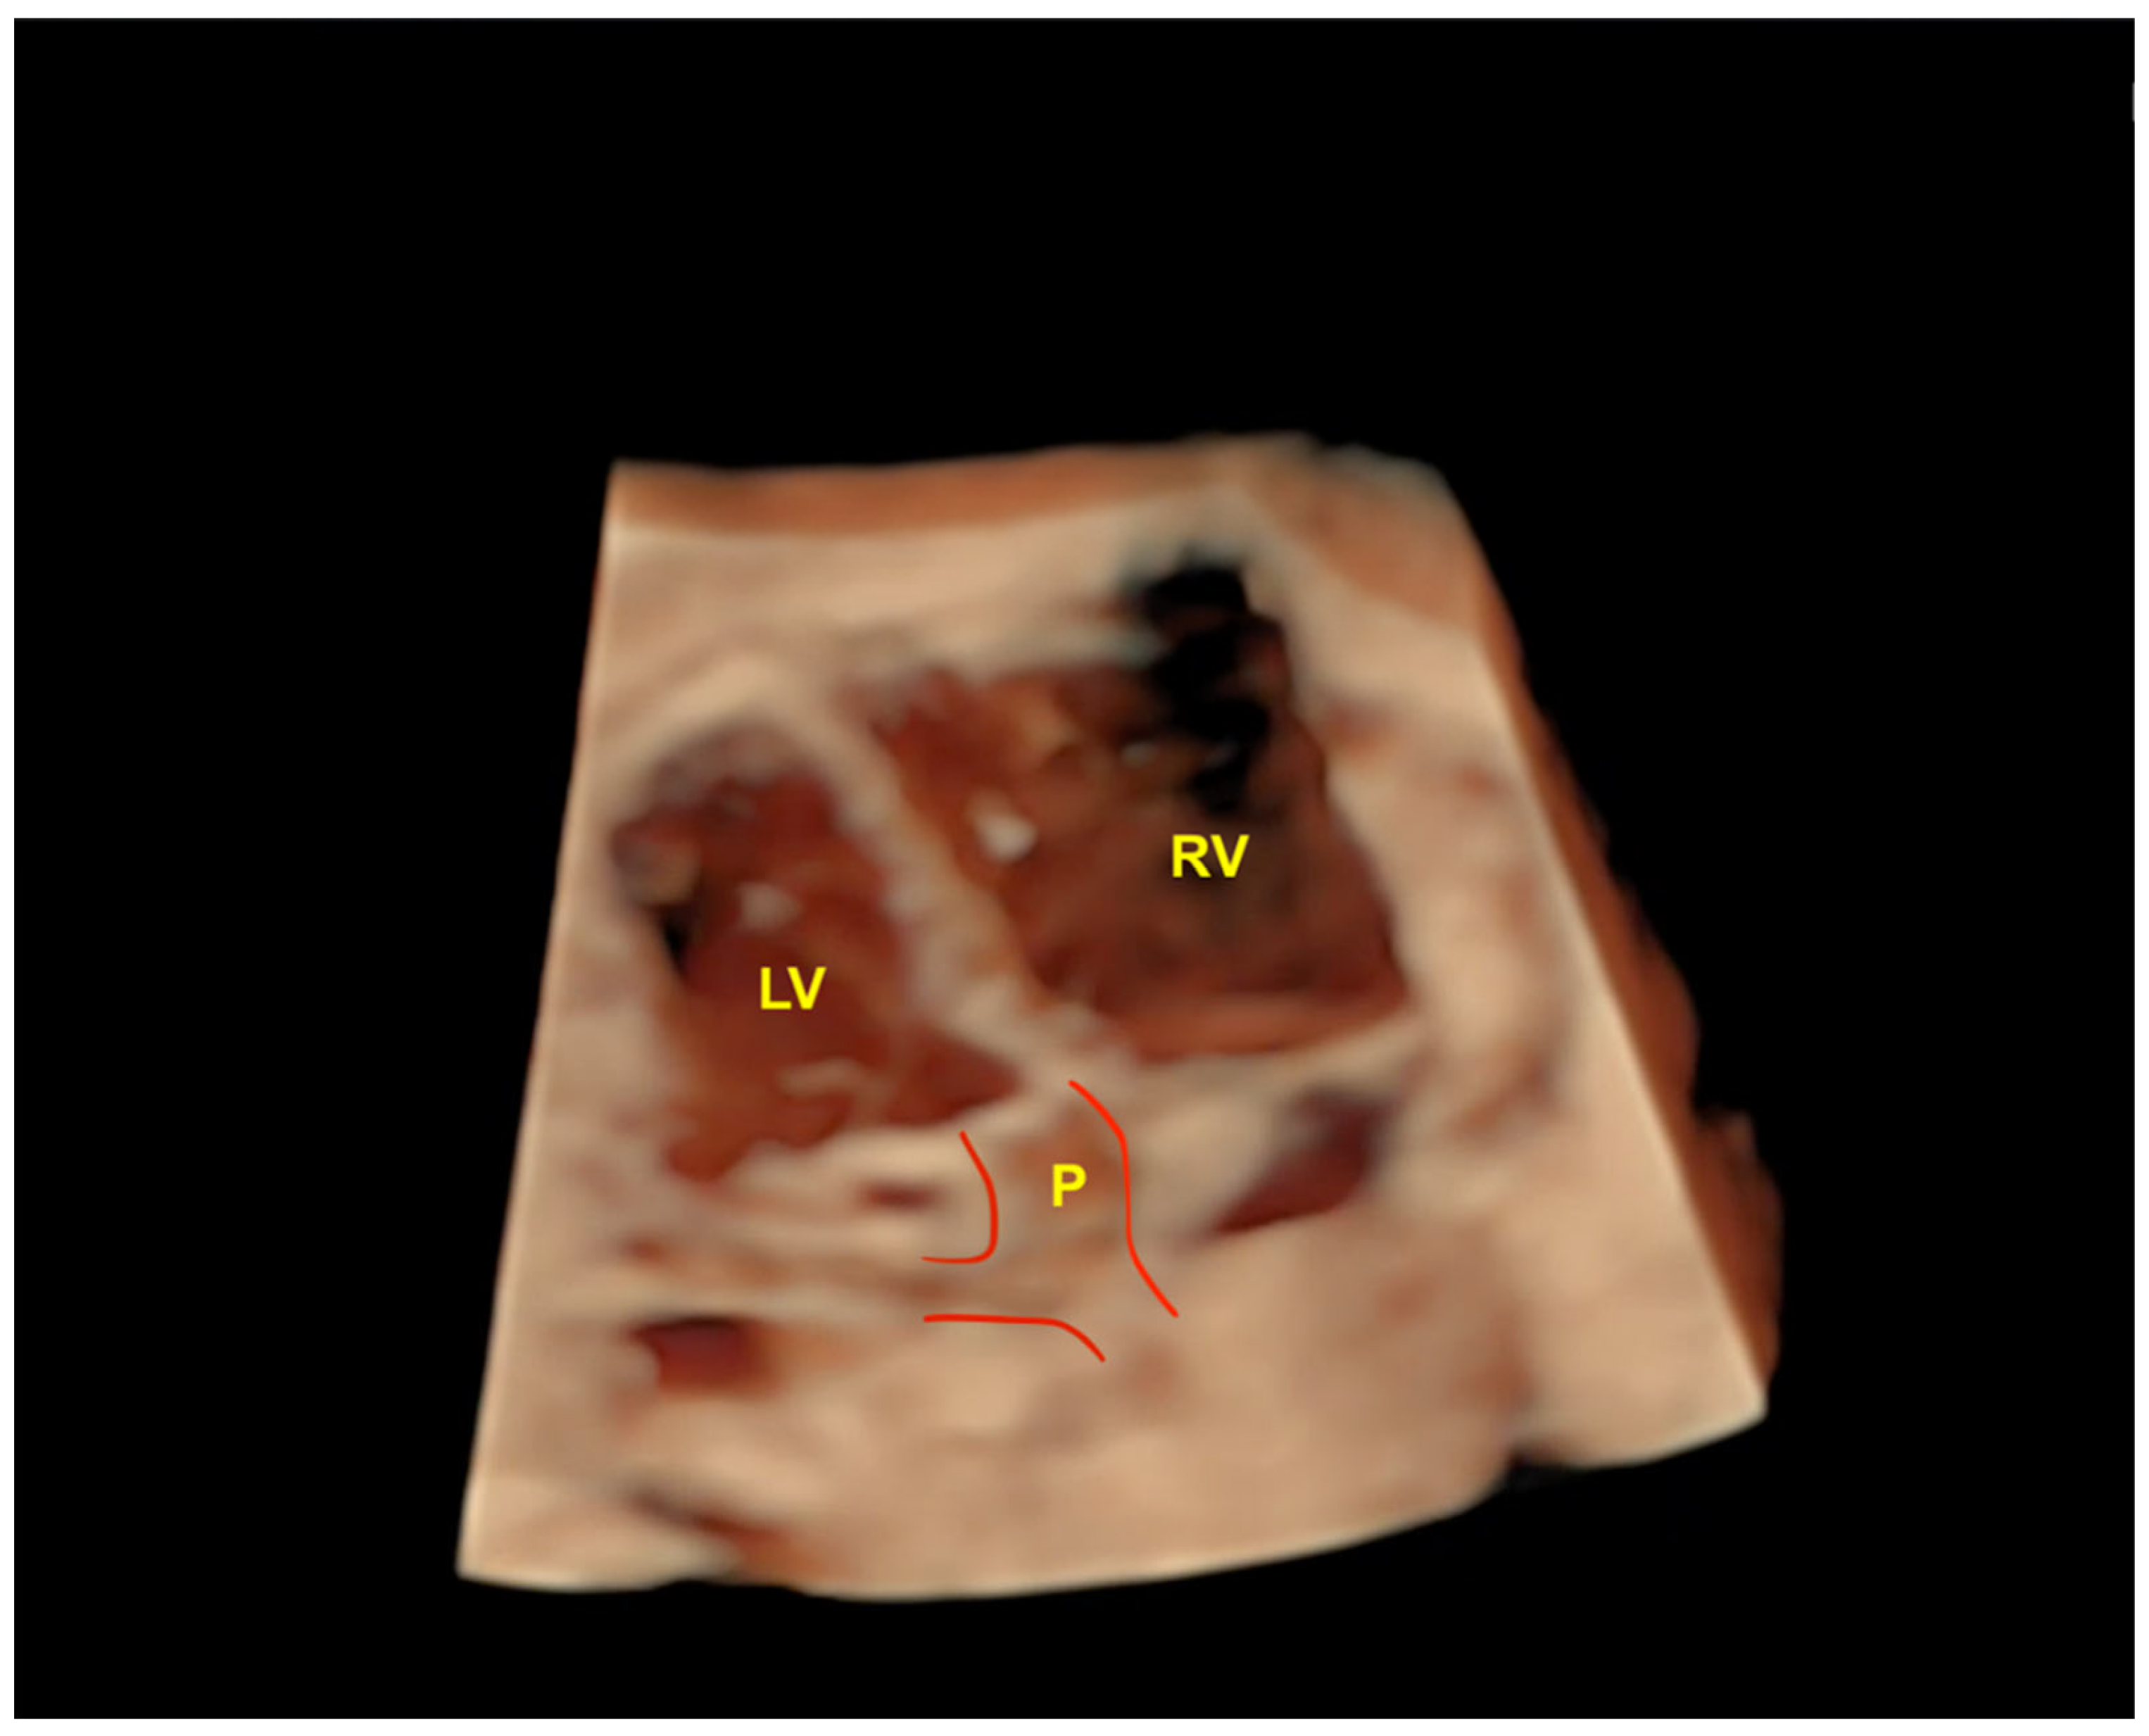

- Rolo LC, Pietrolucci ME, Araujo Júnior E, Barros FS, Nardozza LM, Martina WP; et al. Viewing rate and reproducibility of papillary muscle areas in foetal atrioventricular valves using spatio-temporal image correlation in the rendering mode in congenital heart disease. J Matern Fetal Neonatal Med. 2015, 28, 1375–1380.